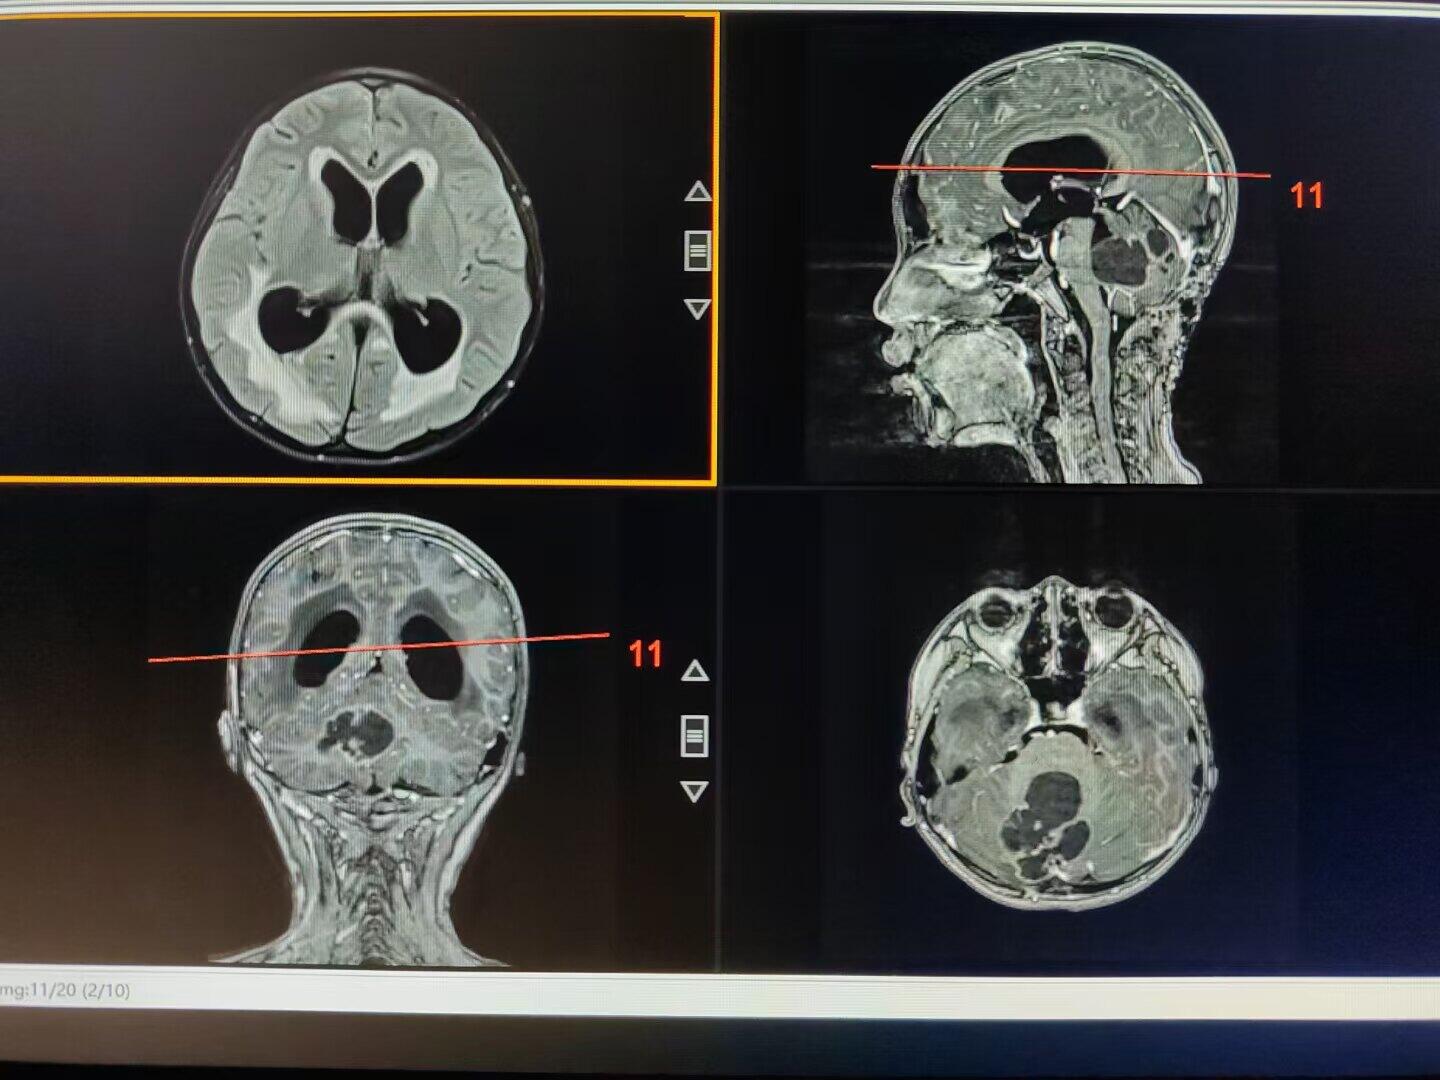

后颅窝占位引起梗阻性脑积水,术前已经出现视力模糊,脑室ommaya测压大于50cm水柱,临时外引流缓解颅压后患儿视力有恢复,后急诊行后颅窝占位切除,术中切除囊性占位、打通中脑导水管、解除脑干压迫,术后脑积水缓解满意,患儿状态良好。